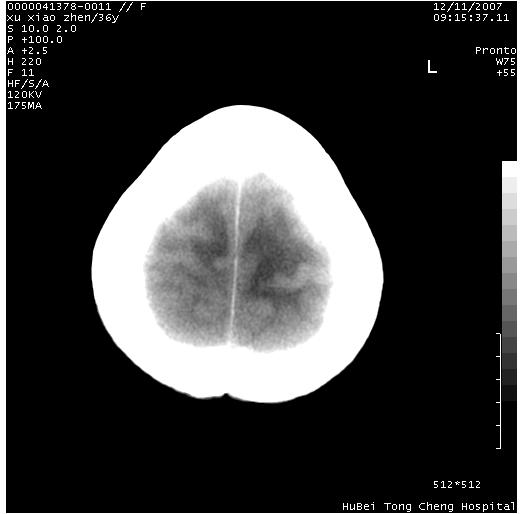

以下是引用wzr在2007-12-12 18:58:00的发言:[br]以脑白质受累,脑肿胀明显,脑室变窄,多考虑炎性改变,建议进一步ce或mri明确.

以下是引用wqs571018在2007-12-12 19:48:00的发言:[br]脑白质受累,脑肿胀明显,脑室变窄,多考虑炎性改变,脑膜炎可能性大;建议mri明确.。